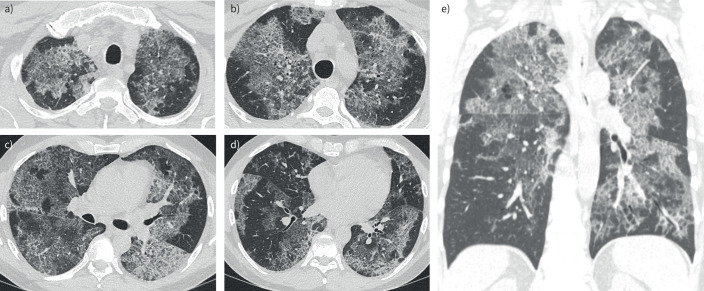

肺泡蛋白沉积症(PAP)是一种罕见的肺部疾病,由表面活性剂在肺泡内积聚引起,可导致呼吸系统症状和气体交换受损。最近的欧洲呼吸学会指南为其诊断和管理提供了基于证据的建议。自身免疫性PAP (aPAP)是最常见的形式,由粒细胞-巨噬细胞集落刺激因子(GM-CSF)自身抗体驱动。推荐的诊断工具包括支气管肺泡灌洗和定量GM-CSF抗体检测。全肺灌洗和吸入GM-CSF是有症状或进展性aPAP的一线治疗方法。利妥昔单抗、血浆置换和肺移植是治疗难治性疾病的选择。建议转介到专家中心接受诊断和治疗指导。这个基于病例的临床医生总结强调了对怀疑或确认PAP的患者的最佳临床方法。

Pulmonary alveolar proteinosis (PAP) is a rare lung disease caused by accumulation of surfactant in the alveoli, leading to debilitating respiratory symptoms and impaired gas exchange. The recent European Respiratory Society guidelines provide evidence-based recommendations for its diagnosis and management. Autoimmune PAP (aPAP) is the most common form, driven by granulocyte-macrophage colony-stimulating factor (GM-CSF) autoantibodies. Recommended diagnostic tools include bronchoalveolar lavage and quantitative GM-CSF antibody testing. Whole lung lavage and inhaled GM-CSF are first-line treatments for symptomatic or progressive aPAP. Rituximab, plasmapheresis, and lung transplantation are options for refractory disease. Referral to expert centres is advised for diagnostic and therapeutic guidance. This case-based summary for clinicians highlights the best clinical approach to patients with suspicion or confirmation of PAP.